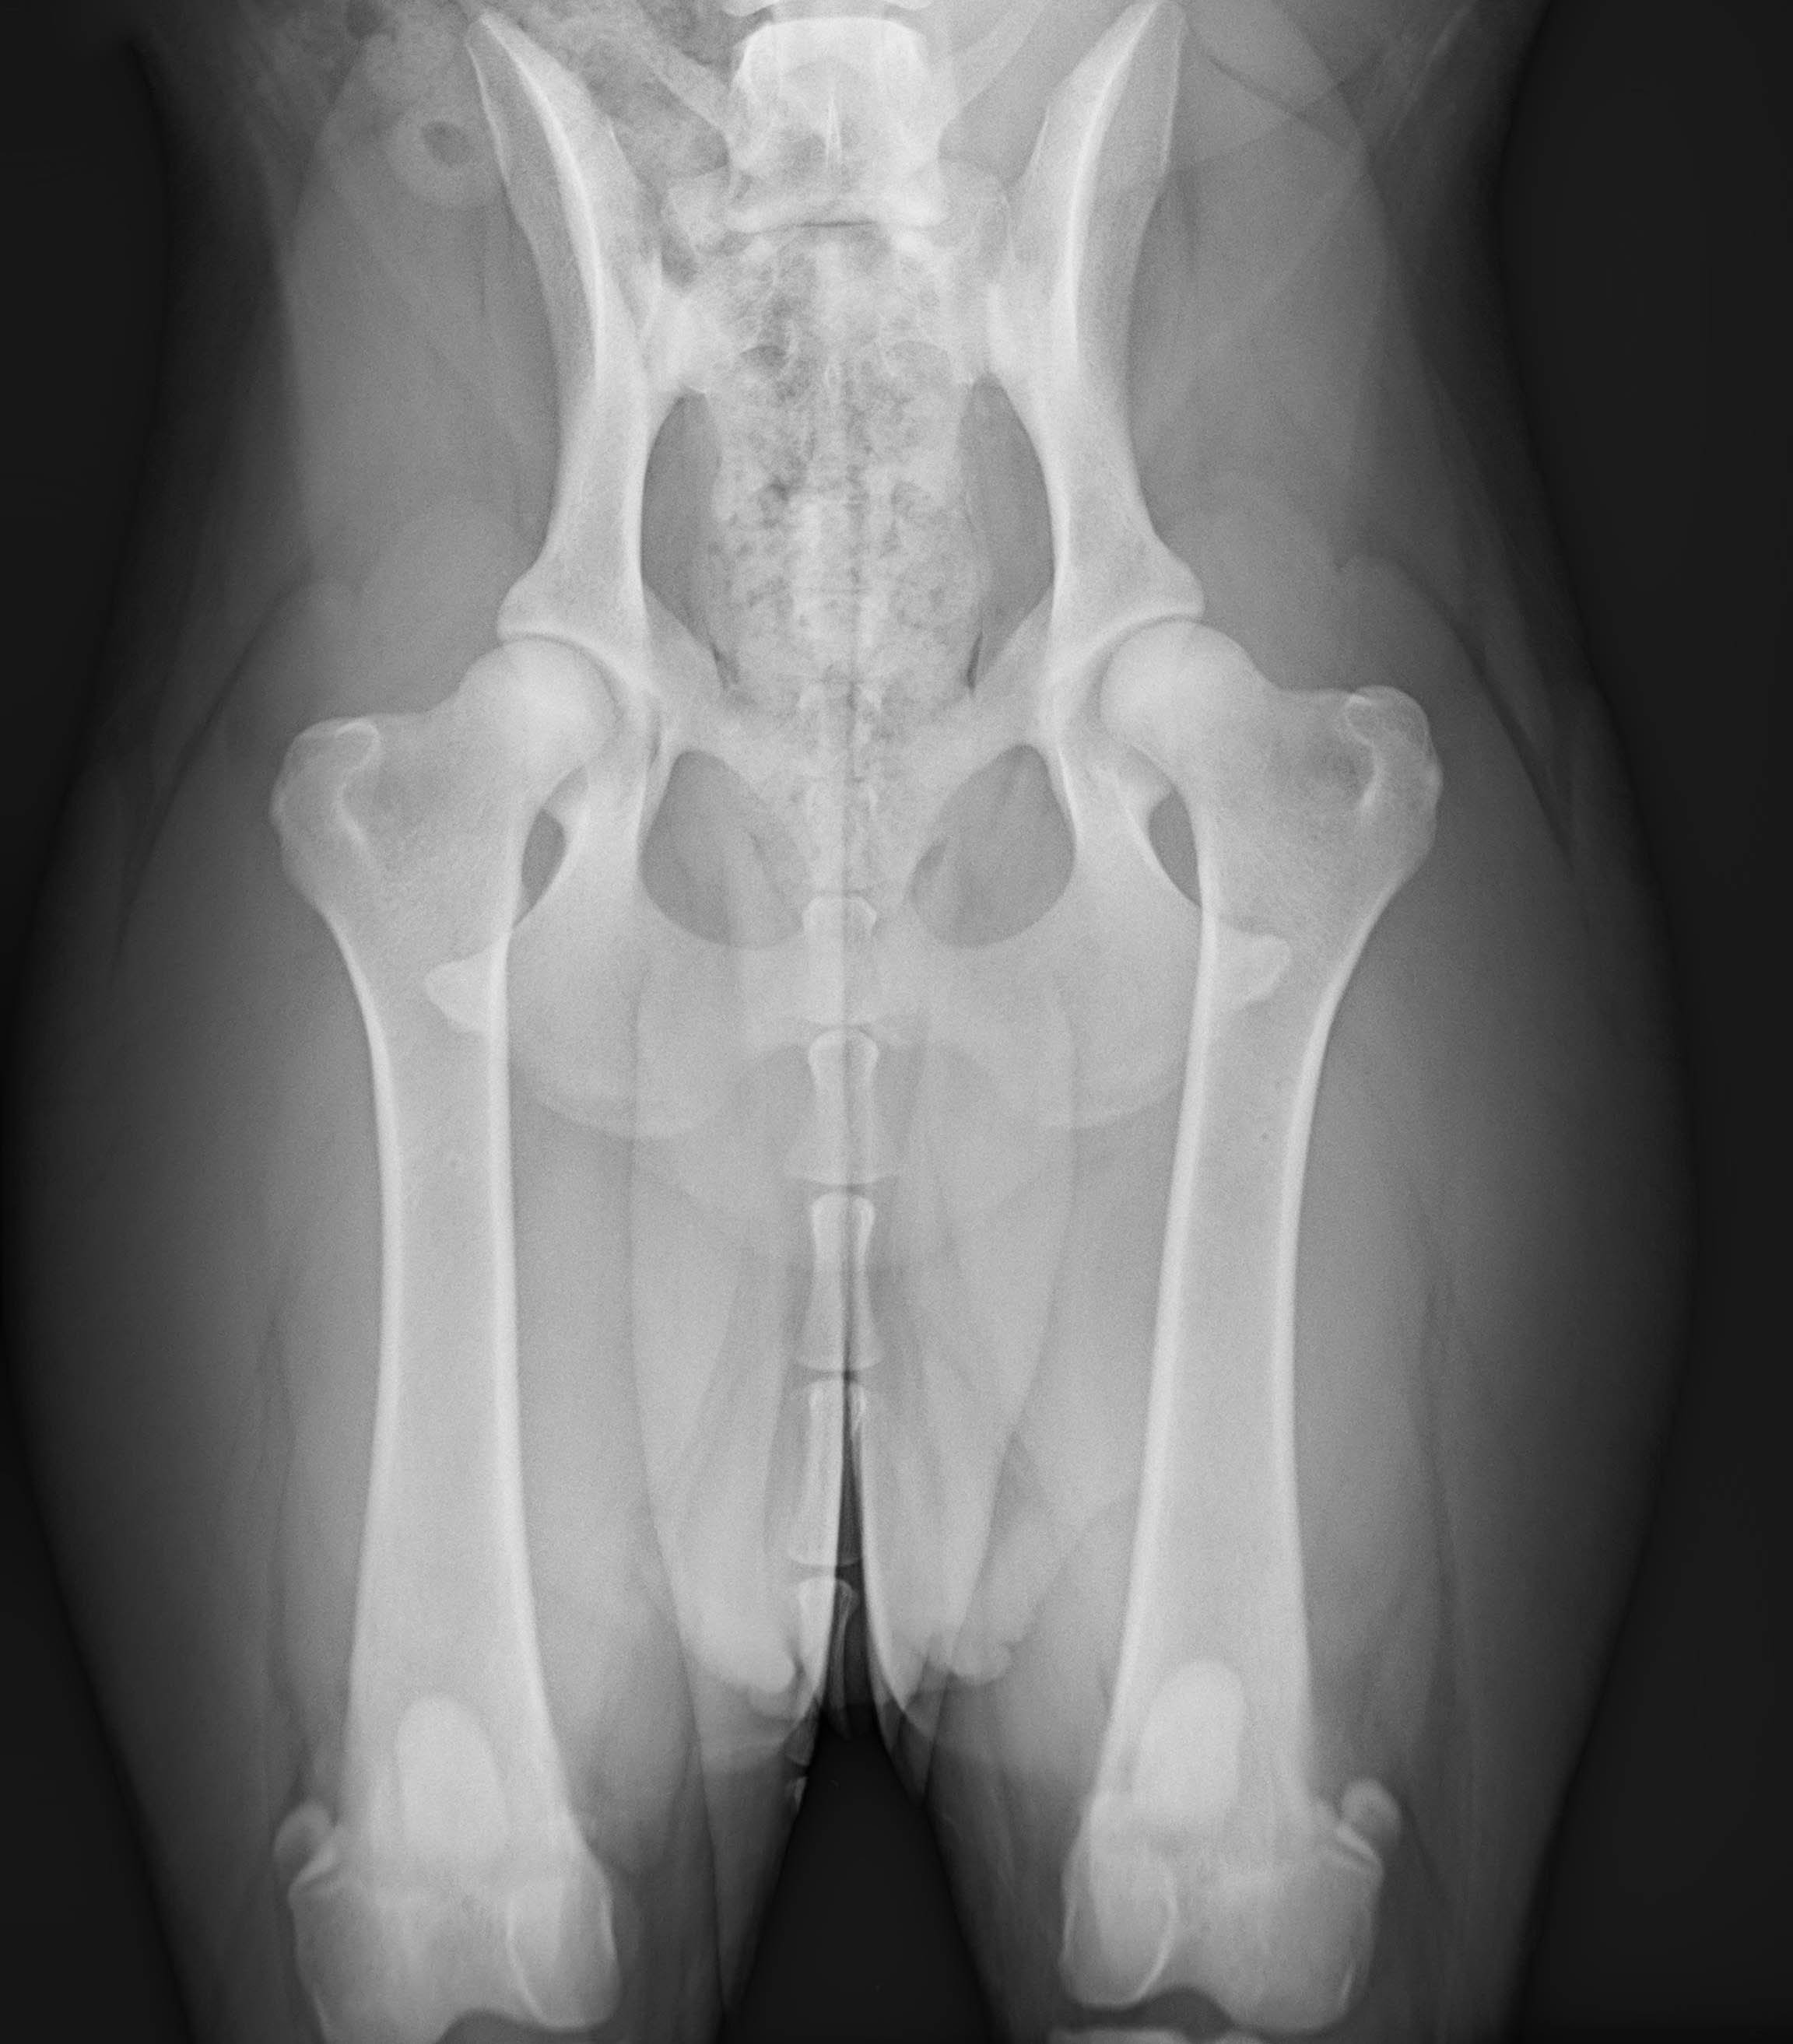

OFA hip radiograph X-ray showing canine hip joint structure for evaluation - Stokeshire Designer Doodles educational content

This isn’t just a hypothetical. A colleague recently shared a radiograph of a beautiful Bernese girl. The image showed round femoral heads, strong coverage, and a clean joint space with no signs of remodeling or arthritis. Most breeders would look at those hips and call them good—maybe even borderline excellent. So why did the official report come back stamped “Fair”?

Several factors contribute to this, including wider hips, rapid weight gain, heavy bone structure, and slower-closing growth plates. Together, these traits can create more hip laxity even in genetically sound dogs. For a Bernese, a “Fair” score may actually represent an individual outperforming the breed’s norm. A “Good” in a Berner is often equivalent to another breed’s “Excellent.” These scores must be interpreted through the lens of the breed, not against an abstract standard.

On the other end of the spectrum are Australian Shepherds. These dogs are known for their deep acetabulum (hip socket), tight joint space, and strong femoral head coverage. Their compact, athletic frames are built for performance.

Aussies typically score in the Good or Excellent range. When they receive a Fair, it is often due to subtle issues such as slight rotation during positioning or a small amount of laxity that only appears under full sedation. An Aussie can appear perfectly sound when awake, but the OFA evaluation reveals passive stability rather than functional movement.